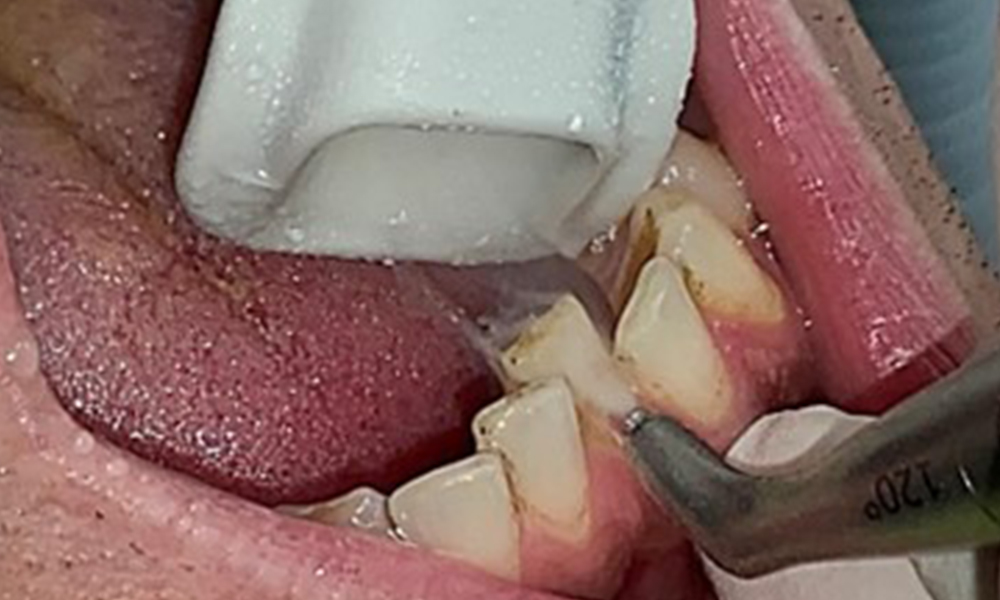

The objective would be to control disease risk by removing supragingival and subgingival biofilm. The instruments can be selected based on patient needs. First, calculus and any concretions must be removed using ultrasonic and/or manual instruments (Fig. 10).

Discolouration caused by nicotine and tea consumption can be removed easily using an air polisher (Fig. 11).

When using more abrasive powder, it is essential to work from a cervical to coronal direction and never point the outlet nozzle towards the gingiva to prevent potential emphysema. Good suction on the contralateral side is essential to reduce aerosol formation (Fig. 12).